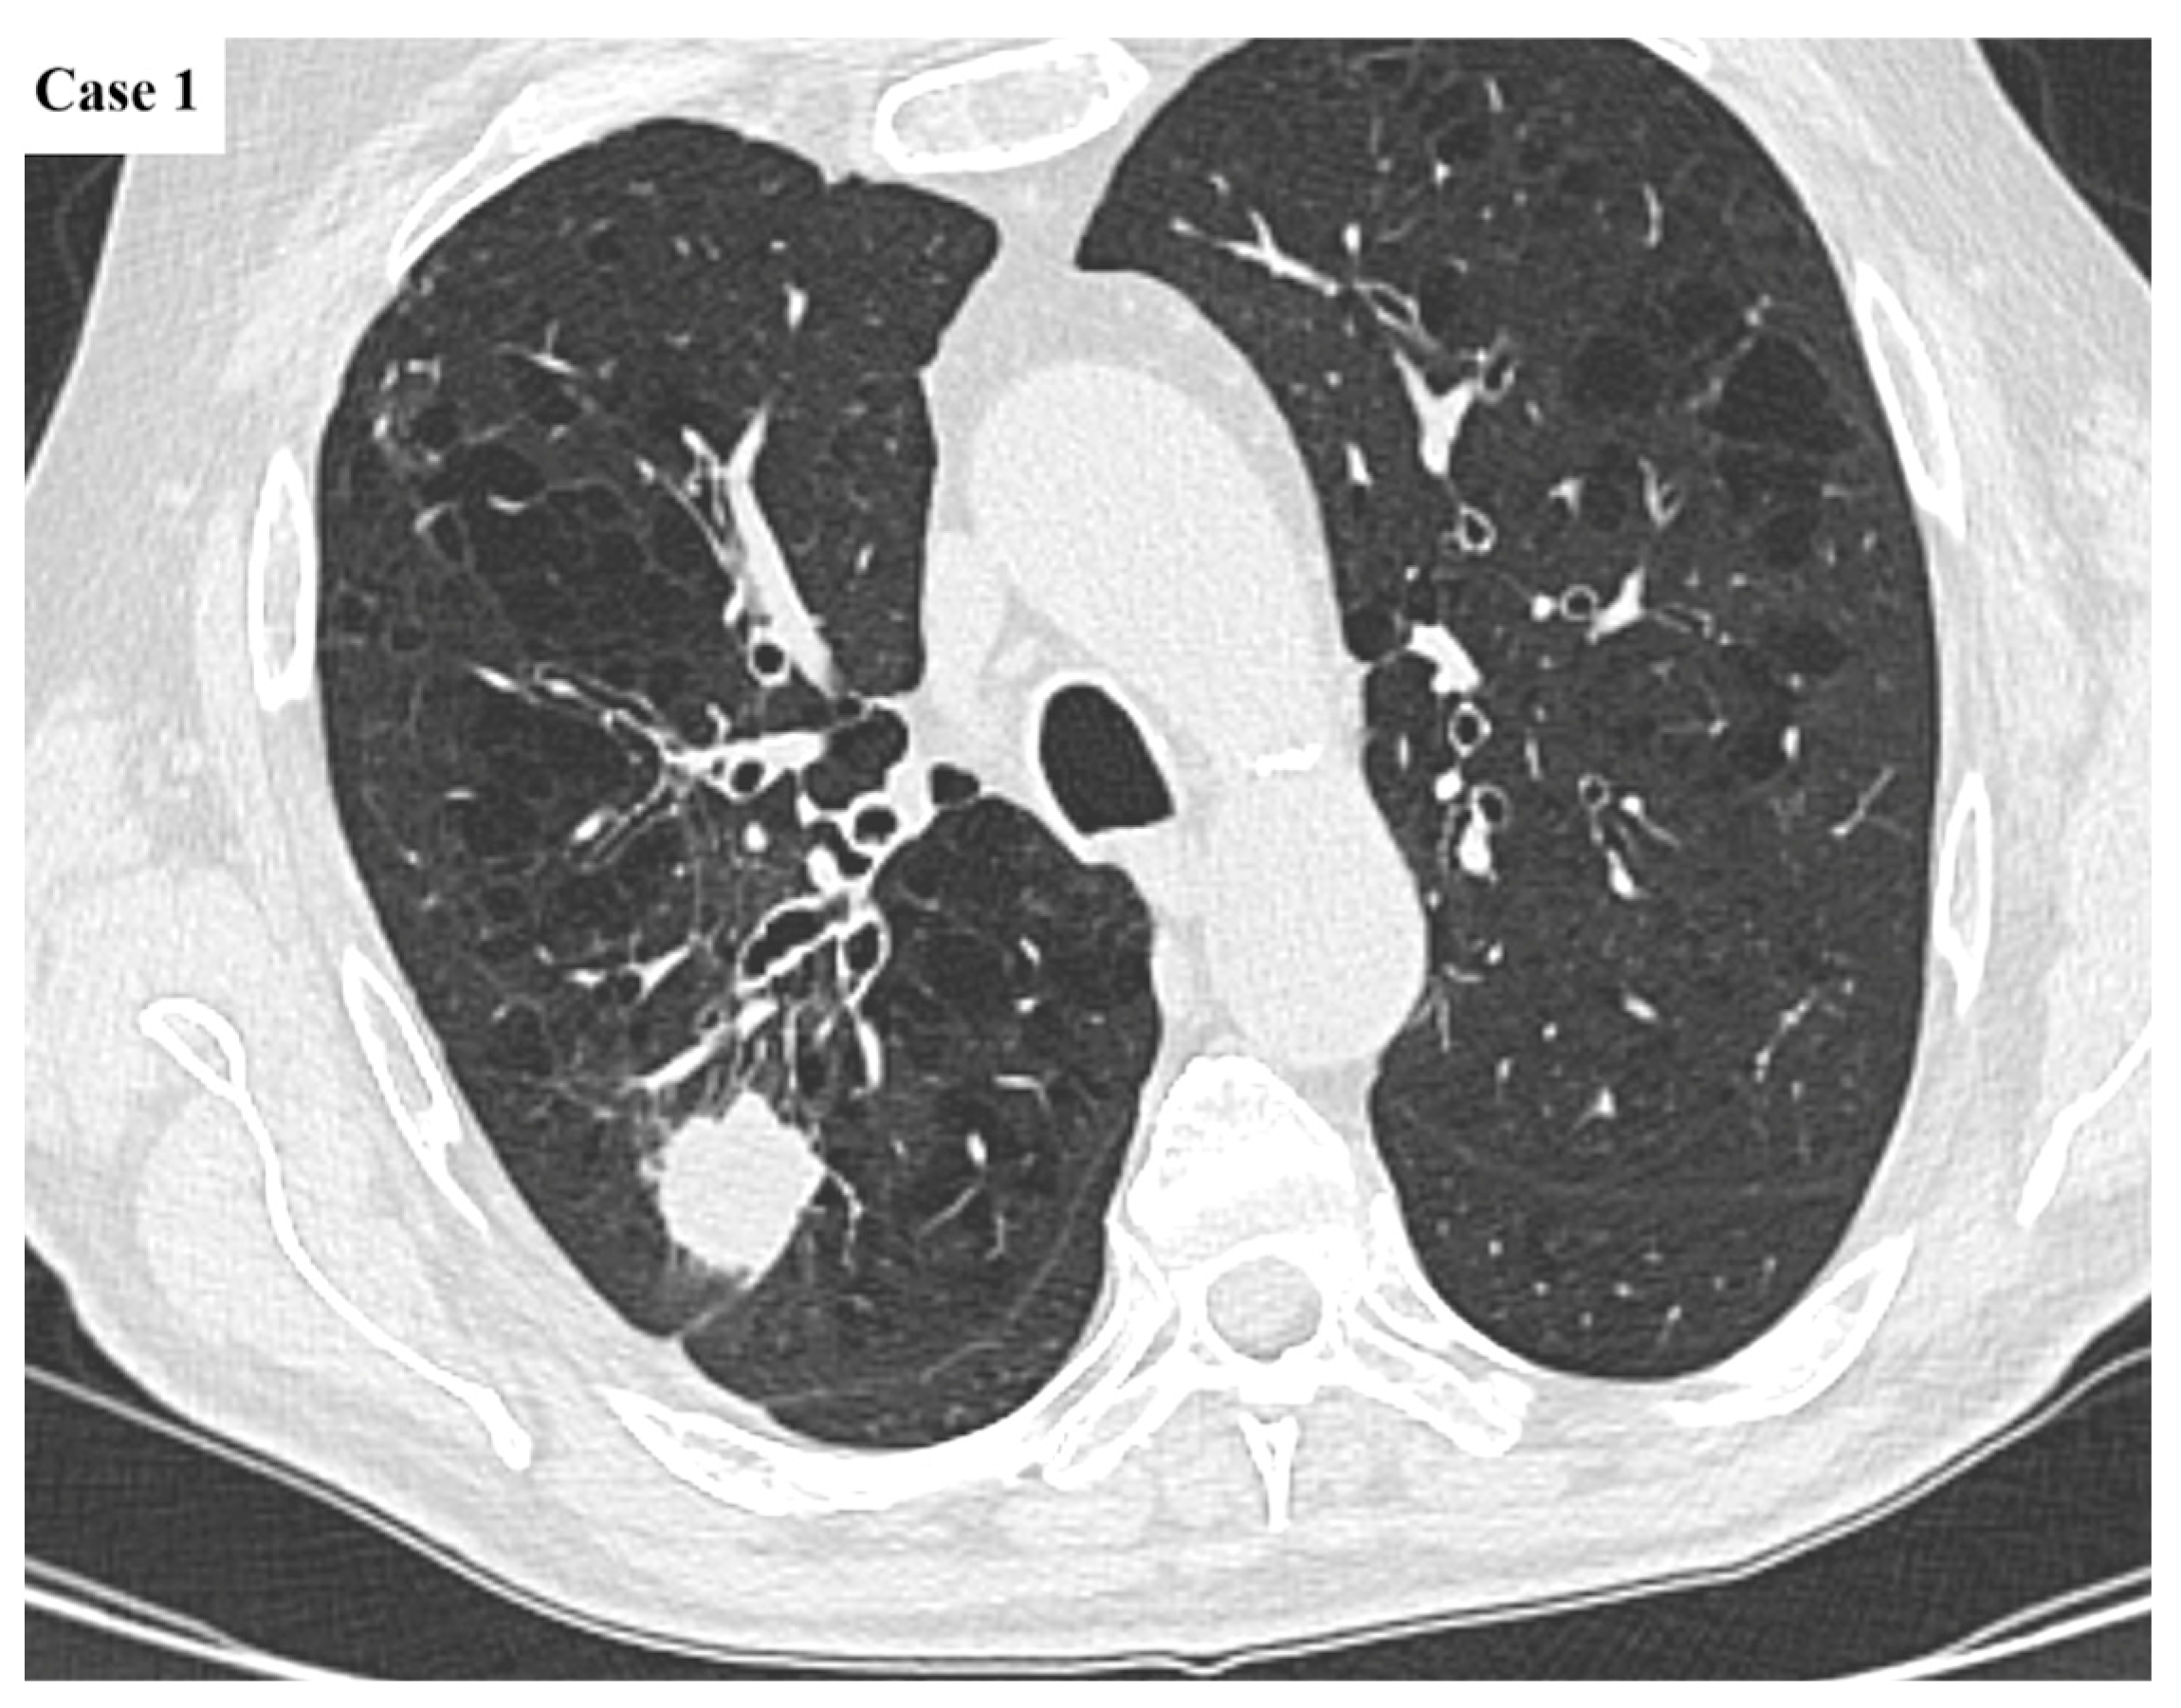

| Imaging features | Spiculated margins: 88% Central necrosis: 38.4% Cavity: 10.4% Lymphangitic spread: 43.2% |